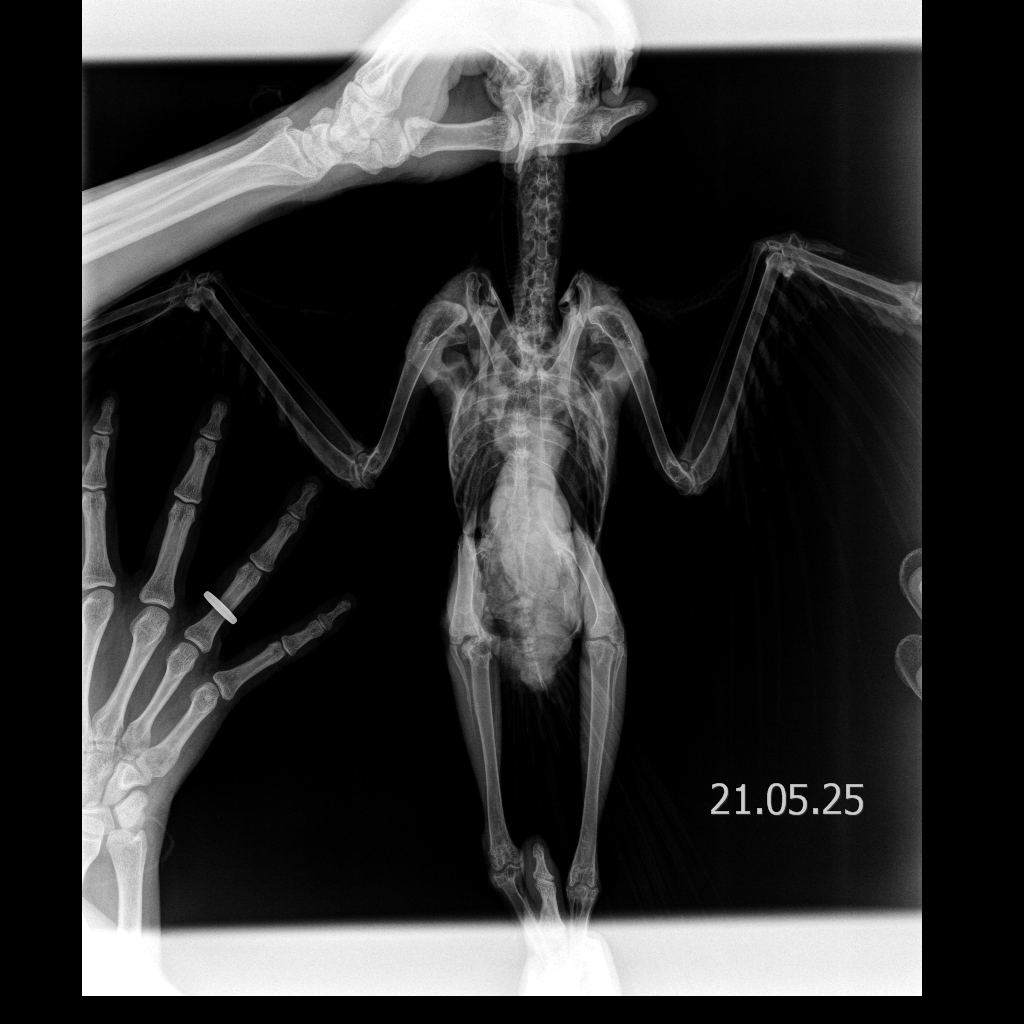

Выяснилось, что у Фени четыре перелома позвоночника в трех отделах и раздроблена спина — врачи сказали, что его нужно однозначно усыплять, потому что птица не выживет и будет мучиться. Обычно при таких травмах животные погибают. Но я отказался усыплять Феню.

Пока конструкция подгонялась и обустраивалась под него, Феня так рассек себе суставы, что прямо из суставных сумок торчали косточки. Помимо этого, спустя три месяца у него начались ужасные воспаления в костях. Изначальные проблемы с позвоночником уже, казалось, были решены, и вот его начала убивать новая беда. Я искал специалистов, но не нашелся никто, кто мог бы помочь.

Еще у Фени был разодран киль до костей: когда он ползал на груди в парке, у него волочились лапки, из-за чего кости распоролись на всю длину. Врачи ничего с этим не делали, но я настоял, чтобы киль зашили. Позже еще попросил зашить и локтевые суставы, но после операции Феня все разодрал и выдрал нитки — остались дырки.

Я решил зашить их сам: заказал хирургический набор с иглами и нитями, проанестезировал Феню. Мне на ум пришла собственная методика, чтобы Феня больше не ковырял, и я сделал так, чтобы нитки торчали не сверху, а были внутри сустава. У Фени действительно все зажило. Правда, у него периодически все еще болит спина так, что он сдирает перья на спине. Суставы у него все равно открыты, но уже не воспалены — теперь там даже растут перышки, хотя раньше было просто мясо.